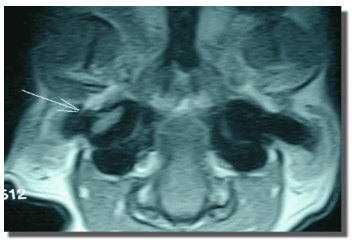

El diagnóstico de las patologías vestibulares centrales requiere métodos de diagnóstico más sofisticados (Figura 10).

Figura 10: RMN de cráneo y cerebro en incidencia L-L (A), y en incidencia D-V (B). Obsérvese la masa de tejido blando en la cavidad del oído medio, compatible con la presencia de pólipos.

La resonancia magnética (RM) es ideal para el estudio del SNC. Es mucho más sensible que la TAC para la evaluación de la fosa posterior cerebral y del tronco encefálico, ya que no es susceptible a los artificios que produce la atenuación de la emisión radiográfica por la porción petrosa del hueso temporal. El análisis del líquido cefalorraquídeo (LCR) puede ser útil en la caracterización de la patología, y es diagnóstico cuando se detectan organismos (por ejemplo Cryptococcus sp) o células tumorales. También puede ser remitido para realizar pruebas serológicas (toxoplasmosis) o cultivo y antibiograma.